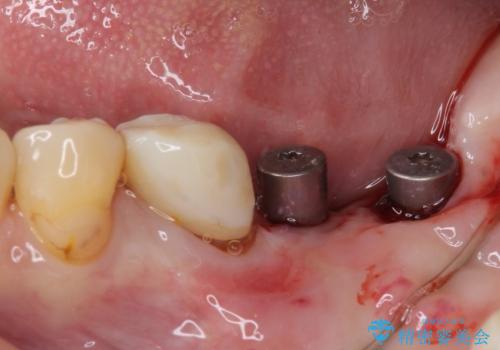

右下は奥歯が抜歯したスペースを塞いでしまい、左下はブリッジの支台歯の1つが破折している状態でした。

並行して左下にはインプラントを埋入し、上顎臼歯部の気になる部分も根管治療などを進めて行き、矯正治療を終えると同時に補綴治療を行うこととしました。

痛みのある奥歯は必要に応じて根管治療を行い、左下インプラントは角化歯肉の移植により清掃性を向上させ、気になっていた部分をしっかりと改善させることができました。